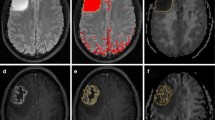

Fifty-nine patients with clinically diagnosed and pathologically proven gliomas were enrolled in this retrospective study. All patients underwent DKI and MAP-MRI scans. Manually outline the ROI of the tumour parenchyma. After delineation, the imaging parameters were extracted using only the data from within the ROI including mean diffusion kurtosis (MK), return-to-origin probability (RTOP), Q-space inverse variance (QIV) and non-Gaussian index (NG), and the differences in each parameter in the classification of glioma were compared. Receiver operating characteristic (ROC) curve analysis was used to evaluate the diagnostic performance of these parameters.

MK, NG, RTOP and QIV were significantly different amongst the different grades of glioma. MK, NG and RTOP had excellent diagnostic value in differentiating high-grade from low-grade glioma, with largest areas under the curve (AUCs; 0.929, 0.933 and 0.819, respectively; P < 0.01). MK and NG had the largest AUCs (0.912 and 0.904) when differentiating grade II tumours from III tumours (P < 0.01) and large AUCs (0.791 and 0.786) when differentiating grade III from grade IV tumours. Correlation analysis of tumour proliferation activity showed that MK, NG and QIV were strongly correlated with the Ki-67 LI (P < 0.001).

MK, RTOP and NG can effectively represent the microstructure of these altered tumours. Multimodal diffusion-weighted imaging is valuable for the preoperative evaluation of glioma grade and tumour proliferative activity.